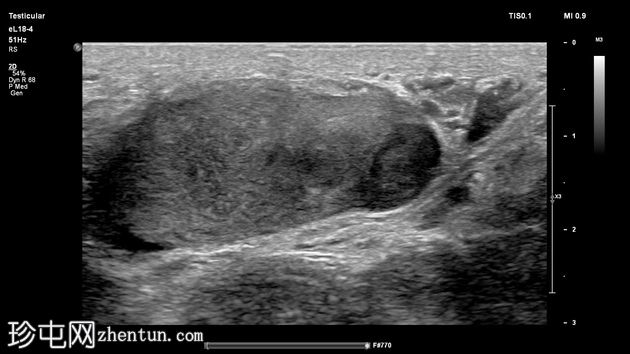

睾丸癌 - 异时性

睾丸下极钝痛,触及硬结。

年龄:65岁

性别:男

右侧阴囊内可见光滑的卵圆形高回声肿块,呈分层状,并伴有进行性声影,符合完整的睾丸假体。

左侧睾丸回声不均匀,可见边界不清的低回声区域,呈地图状分布,实质内散在分布着少量点状彗尾伪影,每个视野少于5个,符合局限性睾丸微石症。

睾丸下极可见一个边界清晰的卵圆形低回声结节,内部可见血流信号。大小为12 x 7 x 15 mm,高度符合睾丸肿瘤影像学表现。

可疑病灶旁可见边缘不规则的异常低回声区域。

附睾小囊肿。

患者既往有15年前因睾丸精原细胞瘤行右侧睾丸切除术的病史。右侧睾丸假体外观完整。结合既往病史和典型的超声检查结果,左侧睾丸病变很可能是异时性睾丸癌,很可能是精原细胞瘤。